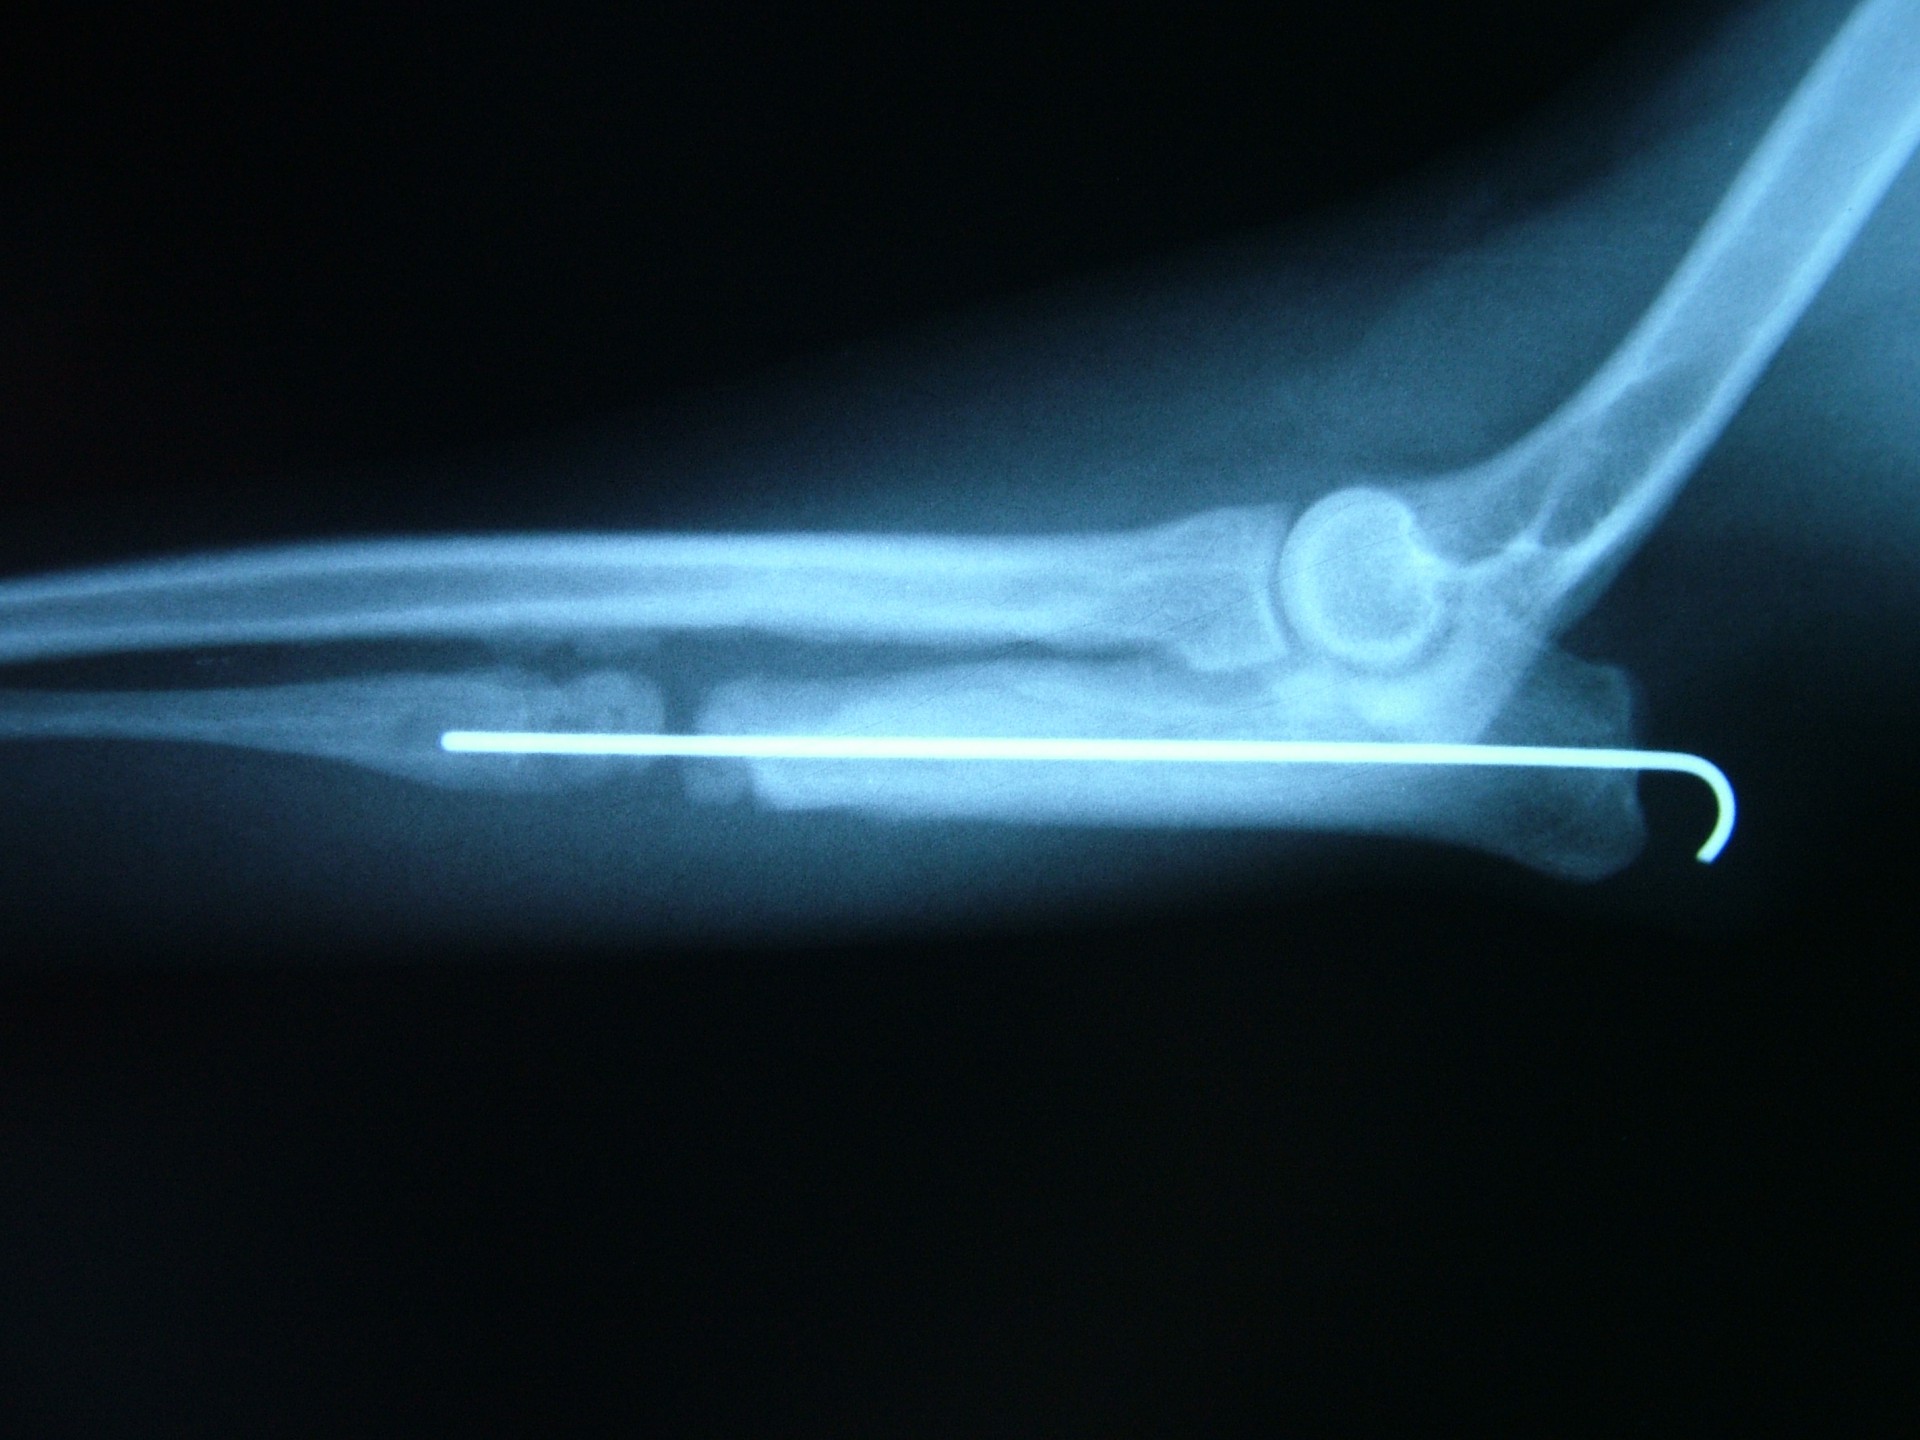

Amennyiben a növekedési zóna lezáródása a végtag deformitásának oka és idejében felismertük a betegséget, a fékként szolgáló könyökcsont egy darabját eltávolítva (ulna osteotomia) az alkarcsont növekedése normalizálódhat. A lassú gyógyulás elengedhetetlen feltétele, hogy az állat még növendék korban legyen, így az alkarcsontnak is legyen lehetősége a növekedésre.Amennyiben a végtag növekedésére már nincs esélyünk, ill. a valgus állás genetikai vagy egyéb traumás eredetű, a műtéti korrekció során a görbült alkarcsontból egy ék kivágásával és az elvágott területek megfelelő irányba helyezését követően osteosynthesis-sel a végtag kiegyenesíthető.

Az alkarcsont alsó vagy felső növekedési zónájának lezáródása esetén a könyökízületben kialakuló inkongruencia az ízület mozgásának fájdalmasságához, a mozgáspálya beszűküléséhez vezet. Paradox módon az ilyen elváltozás esetén is (mivel az alkarcsont a teherviselő csont) a könyökcsont osteotomiájával, annak növekedésének korlátozásával gyógyítjuk a beteget.

Az idejében észrevett elváltozás esetén, - amennyiben a csövescsontok növekedése még nem állt le -, az ízület normalizálódik, az eredeti funkció visszaáll.Súlyos fokú inkongruencia kialakulása esetén az ízületi funkció már nem állítható vissza. Azokban az esetekben, amikor a súlyos ízületi elváltozás fájdalommal jár az ízület bemerevítésével (arthrodesis) a fájdalom megszüntethető.